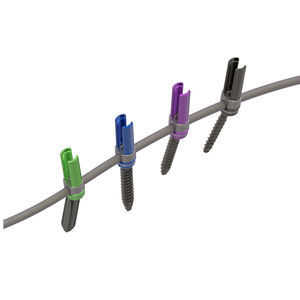

... Tornillo de gran ángulo Reduce la dificultad de colocar la varilla Rosca de ángulo inverso Evita la rosca cruzada Reduce el espacio ocupado Fijar temporalmente el tornillo Mantener la alineación Fácil de colocar la varilla Cabeza de tornillo amortiguadora Fijar ...